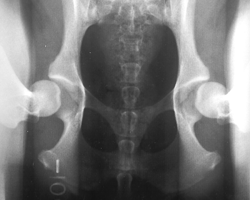

3. gestreckte Hüfte

Die Hintergliedmaße des Patienten sind gestreckt. PennHIP nutzt diese Aufnahme, um Anzeichen einer Arthrose im Sinne einer degenerativen Gelenkserkrankung zu identifizieren. Traditionelle HD-Untersuchungen werden oftmals nur in dieser Position durchgeführt. Bei einem klassischen Verfahren würde dieser Patient gut abschneiden, da in der gestreckten Aufnahme kein Hinweis auf eine Arthrose oder auch Lockerheit der Hüfte zu finden ist. In der 1. Distraktions Aufnahme hingegen sieht man, dass die Hüfte nicht den straffen Eindruck vermittelt, den sie in der 3. gestreckten Aufnahme zu erwecken versucht. Die Hüfte ist "locker". Somit steigt die Gefahr einer Hüftgelenksdysplasie, in vielen Studien nachgewiesen, deutlich an. Dieser Hund wird mit großer Wahrscheinlichkeit in seinem weiteren Leben eine Arthrose im Bereich des Hüftgelenkes entwickeln.